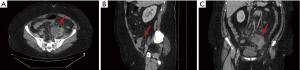

Upon presentation, vitals were within normal limits. Physical examination revealed a soft, non-distended abdomen with mild tenderness in the left lower quadrant on deep palpation but no guarding or rebound tenderness. A pelvic exam was negative for mucopurulent discharge or cervical motion tenderness. Initial laboratory investigation showed marked leukocytosis (19.3 k/mm3) with neutrophilia (80.9%). A pregnancy test was negative, as were nucleic acid amplification tests (NAAT) for Chlamydia trachomatis and Neisseria gonorrhoeae. Urinalysis was unremarkable. An in-house abdominal-pelvic CT with intravenous (IV) contrast was completed to assess appropriateness of percutaneous drainage by interventional radiology. It revealed fat stranding and edema within the pelvis and a left adnexal fluid collection measuring 6.8 cm, containing septations as well as air, and adjacent free intraperitoneal air without any presence of enlarged lymph nodes (Figure 1). The position of the adnexal lesion and adjacent bowel precluded percutaneous drainage. Transvaginal ultrasound was not performed, as the outside facility CT scan already established the presence of an adnexal mass, which was initially concerning for TOA. Furthermore, given the patient’s nonspecific symptoms, the decision was made to proceed with a CT scan with IV contrast to evaluate for possible gastrointestinal pathologies